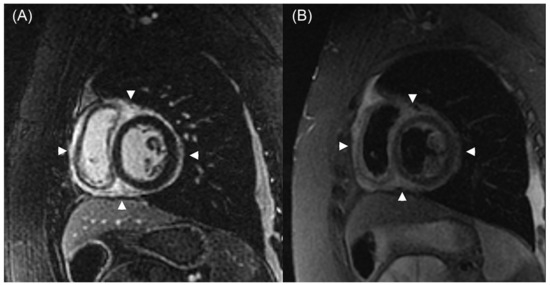

5.1. Cardiac Magnetic Resonance Imaging (CMR)

- Chih, S.; Ross, H.J.; Alba, A.C.; Fan, C.S.; Manlhiot, C.; Crean, A.M. Perfusion cardiac magnetic resonance imaging as a rule-out test for cardiac allograft vasculopathy. Am. J. Transplant. 2016, 16, 3007–3015. [Google Scholar] [CrossRef]

- Quinn, S.; Catania, R.; Appadurai, V.; Wilcox, J.E.; Weinberg, R.L.; Lee, D.C.; Carr, J.C.; Markl, M.; Allen, B.D.; Avery, R. Cardiac MRI in heart transplantation: Approaches and clinical insights. Radiographics 2025, 45, e240142. [Google Scholar] [CrossRef] [PubMed]

- Miller, C.A.; Sarma, J.; Naish, J.H.; Yonan, N.; Williams, S.G.; Shaw, S.M.; Clark, D.; Pearce, K.; Stout, M.; Potluri, R.; et al. Multiparametric cardiovascular magnetic resonance assessment of cardiac allograft vasculopathy. J. Am. Coll. Cardiol. 2014, 63, 799–808. [Google Scholar] [CrossRef]

- Abbasi, M.A.; Blake, A.M.; Sarnari, R.; Lee, D.; Anderson, A.S.; Ghafourian, K.; Khan, S.S.; Vorovich, E.E.; Rich, J.D.; Wilcox, J.E.; et al. Multiparametric cardiac magnetic resonance imaging detects altered myocardial tissue and function in heart transplantation recipients monitored for cardiac allograft vasculopathy. J. Cardiovasc. Imaging 2022, 30, 263–275. [Google Scholar] [CrossRef]